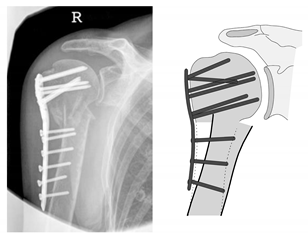

| Complication Type | Exemplary Images by X-rays or Pattern Images | Definition |

|---|---|---|

| 1 | ![]() | Complication Type 1 is defined by a mild, stable varus or valgus displacement (<20°) of the humeral head without resulting in a screw cutout through the humeral head cortex. |

| 2a | ![]() | Complication Type 2a is defined by varus displacement (<20°) of the humeral head associated with screw cutout through the humeral head cortex. The head sintering is considered relatively stable and non-progressive. |